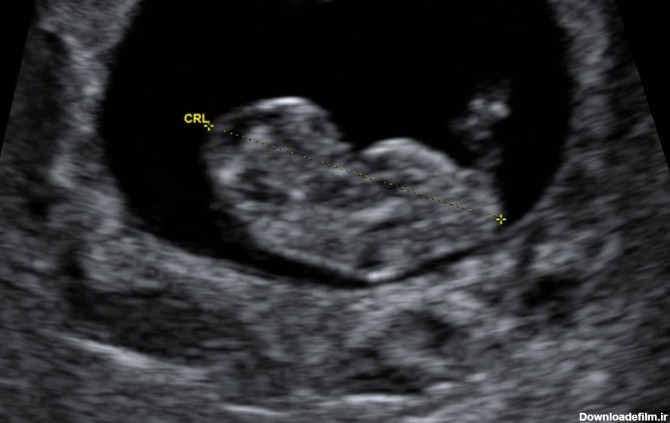

عکس جنین پسر هفت هفته

عکس جنین پسر در سونوگرافی فقط از نظر اندام تناسلی با عکس جنین دختر متفاوت است که تصویر آن را در این متن خواهید دید.

در هفته هشتم بارداری علائمی مانند تهوع، تکرر ادرار و سرگیجه بیشتر می شود. اجزای صورت جنین، پاها و بازوها شکل می گیرند.